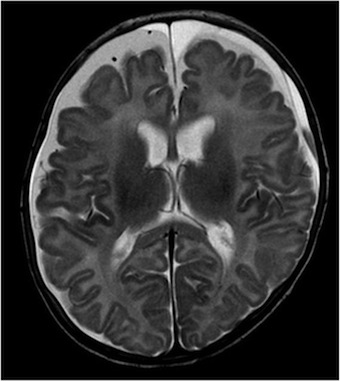

Per un miglior inquadramento clinico è stata pertanto posta indicazione all’esecuzione di RM encefalo. L’esame ha mostrato falde sottodurali intorno agli emisferi cerebrali di natura subacuta o cronica, emorragie in sede subaracnoidea e una sottile componente emorragica in fossa cranica posteriore dietro del cervelletto (Figura 1).

Nel sospetto di shaken baby syndrome è stata richiesta la visita oculistica con fundus oculi, che ha rilevato numerose emorragie diffuse su tutto l’ambito retinico, bilaterali e la skeletal survey che è risultata negativa. A necessario completamento diagnostico è stato indagato il profilo della coagulazione e sono stati eseguiti esami metabolici per escludere alcune patologie come la glutarico aciduria e la sindrome di Menkes, che possono essere responsabili di quadri clinici simili a quello descritto, e che sono ancora in corso.

Il sospetto di SBS non deve essere dimenticato quando ci troviamo di fronte a un neonato o un piccolo lattante con segni neurologici senza cause apparenti e che presenti i fattori di rischio. Ruolo fondamentale per la diagnosi è rappresentato dalle neuroimmagini, in particolare la RM encefalo e rachide che, oltre a mostrare le lesioni caratteristiche (ematomi subdurali, le emorragie subaracnoidee, lesioni ipossico-ischemiche), può rilevare a livello cervicale altri segni tipici del trauma cervicale della SBS (ematomi spinali, edema dei tessuti molli e dei legamenti cervicali, lesioni alle vertebre cervicali). La SBS ha una prognosi severa: infatti circa il 25-30% dei pazienti muore, mentre il 60-70% mostra spesso esiti.